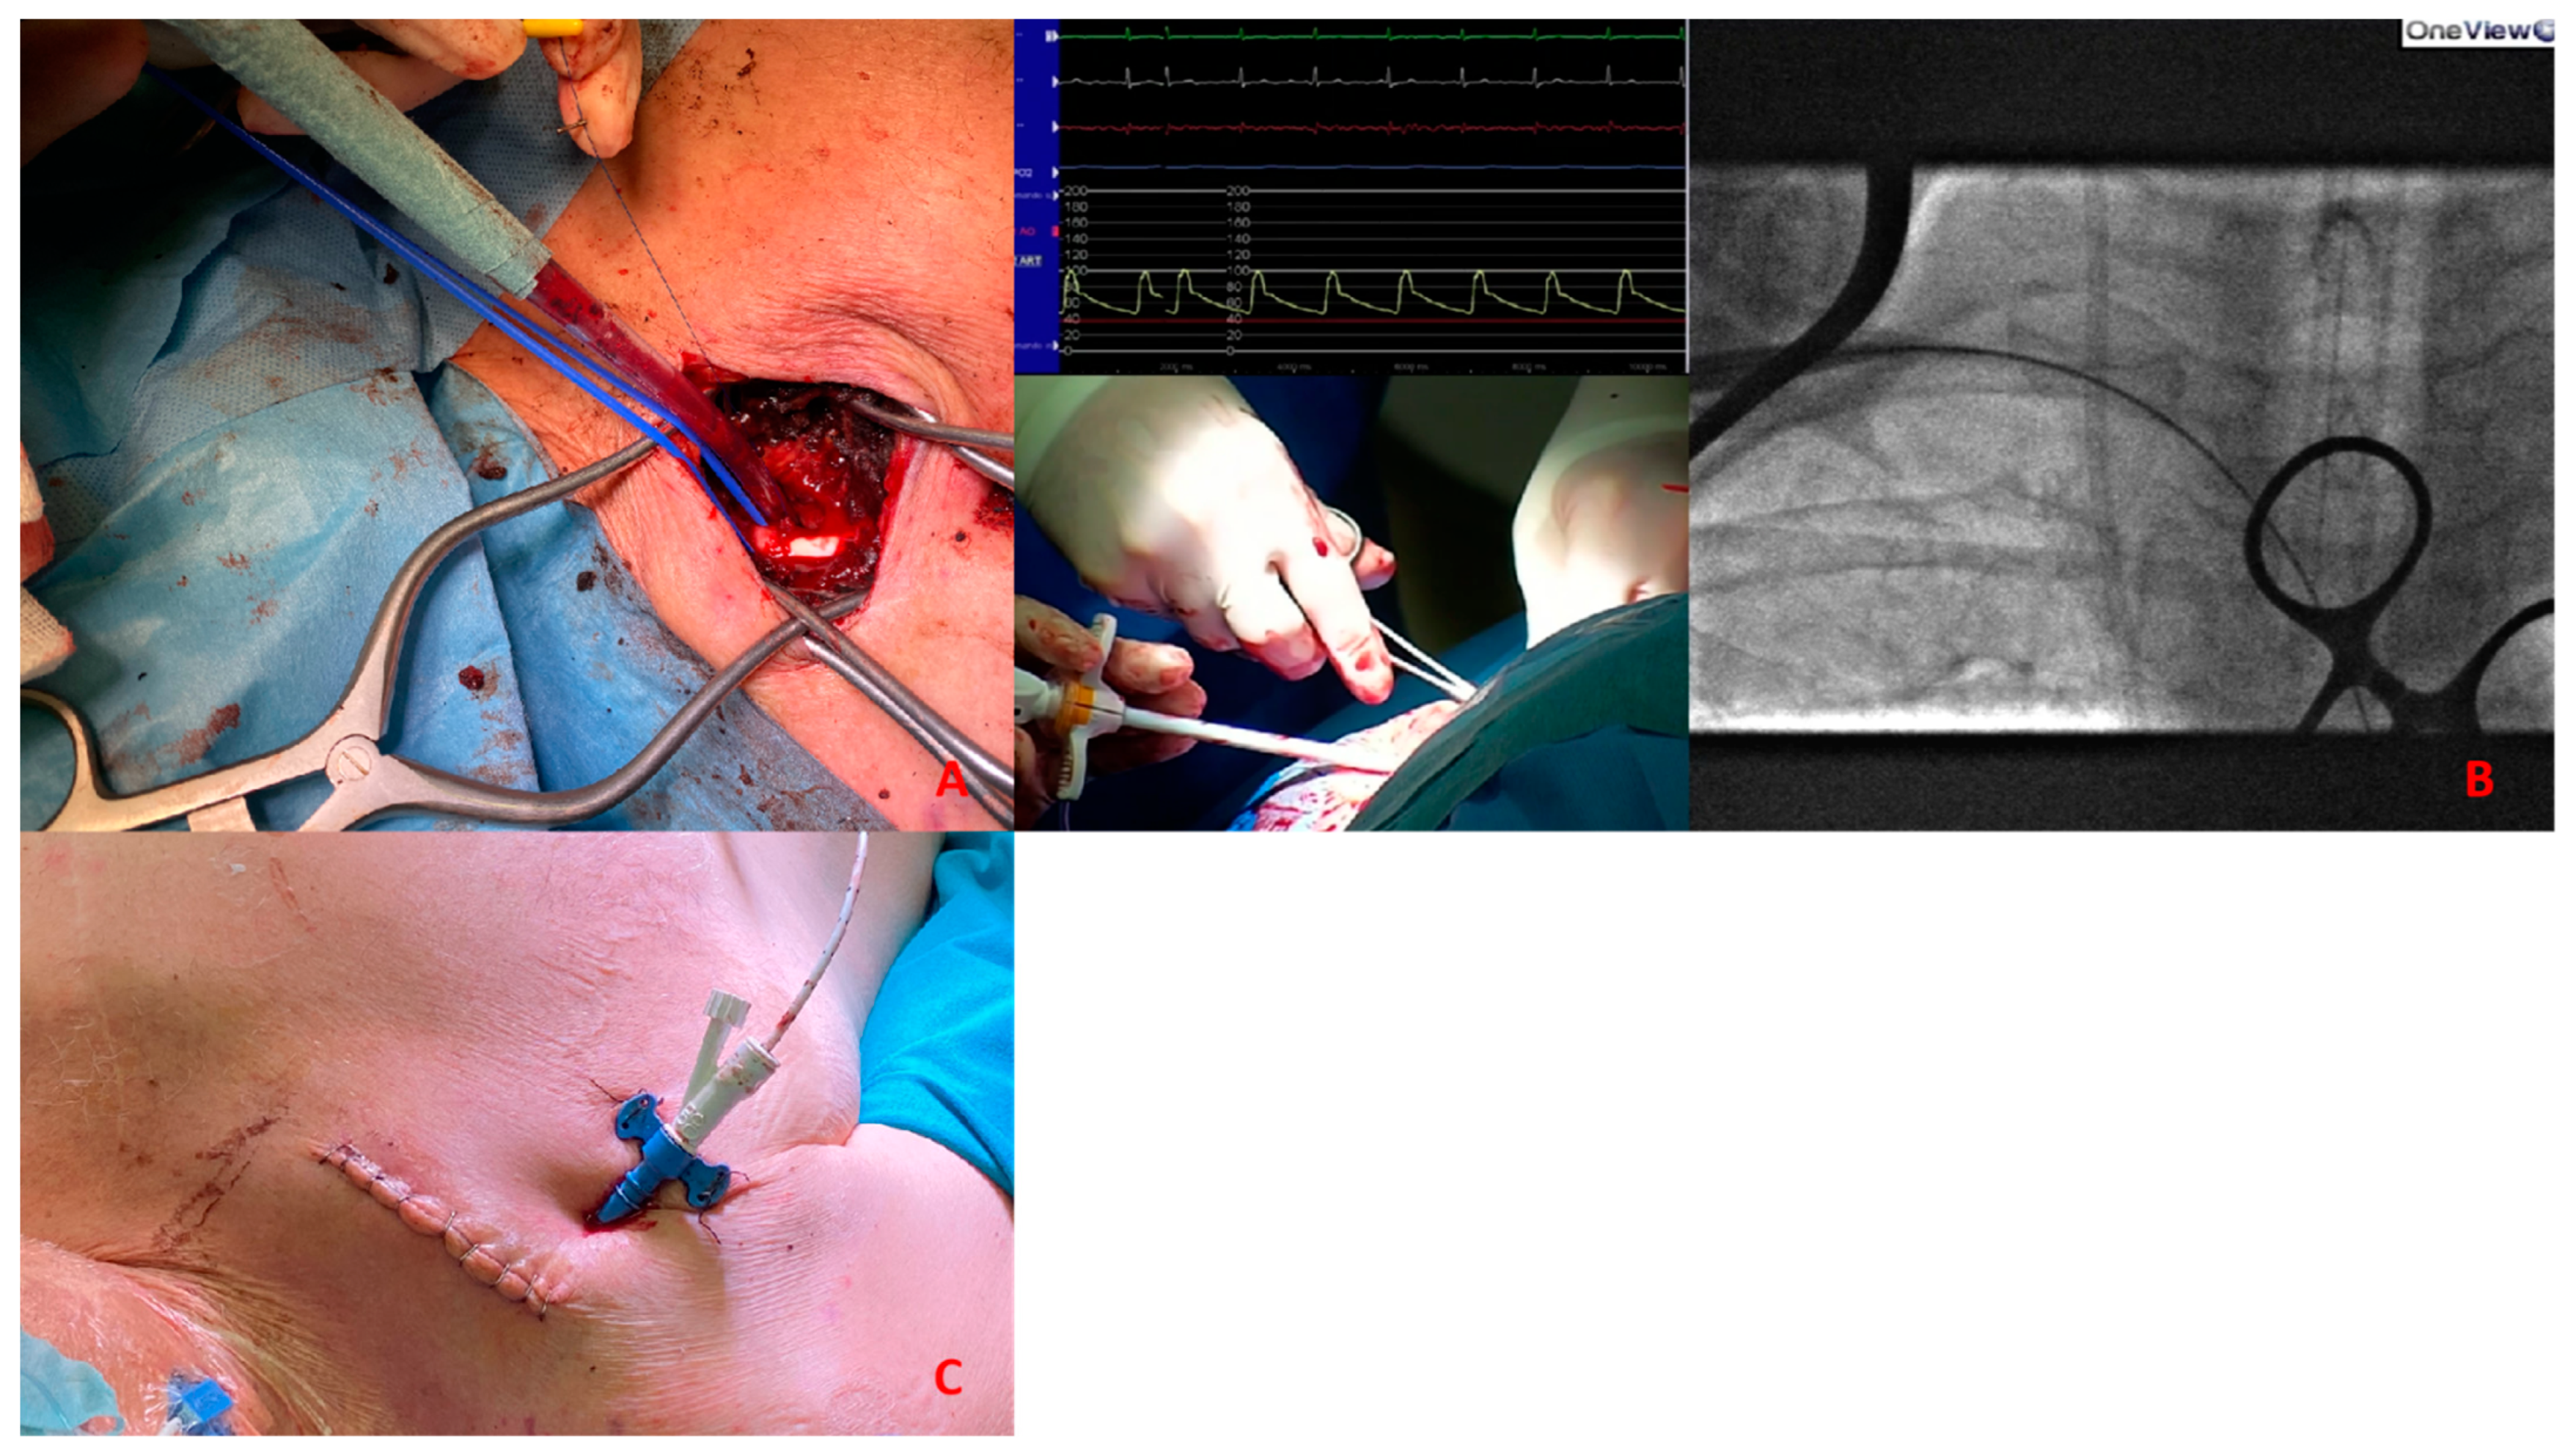

3.2. Transaxillary/Subclavian Access

The sheath is introduced through the axillary and subclavian arteries into the aorta. The normal caliber of the axillary artery ranges from 6 to 7 mm, allowing the insertion of sheaths and catheters until 18 Fr. The axillary artery has been shown to be an acceptable alternative access site for pMCS if conventional access cannot be used [11,12].

The access could be percutaneous Figure 6 or with surgical cutdown. Percutaneous access should be performed at the distal edge of the first segment or the proximal end of the second segment with the needle crossing the pectoralis minor muscle in order to obtain a compressible site corresponding with the second rib. Surgical cutdown is usually performed with a vascular graft anastomosed to the vessel with the insertion of a short sheath in the conduit. Alternatively, it could be performed with surgical exposure of the vessel.

In this paper we would to propose our decisional algorithm Figure 7 in three different settings.

(A). Surgical exposure of subclavian artery. (B). Insertion of Impella CP sheath under fluoroscopy guidance. (C). Placement of the sheath after tunnellization under the skin.